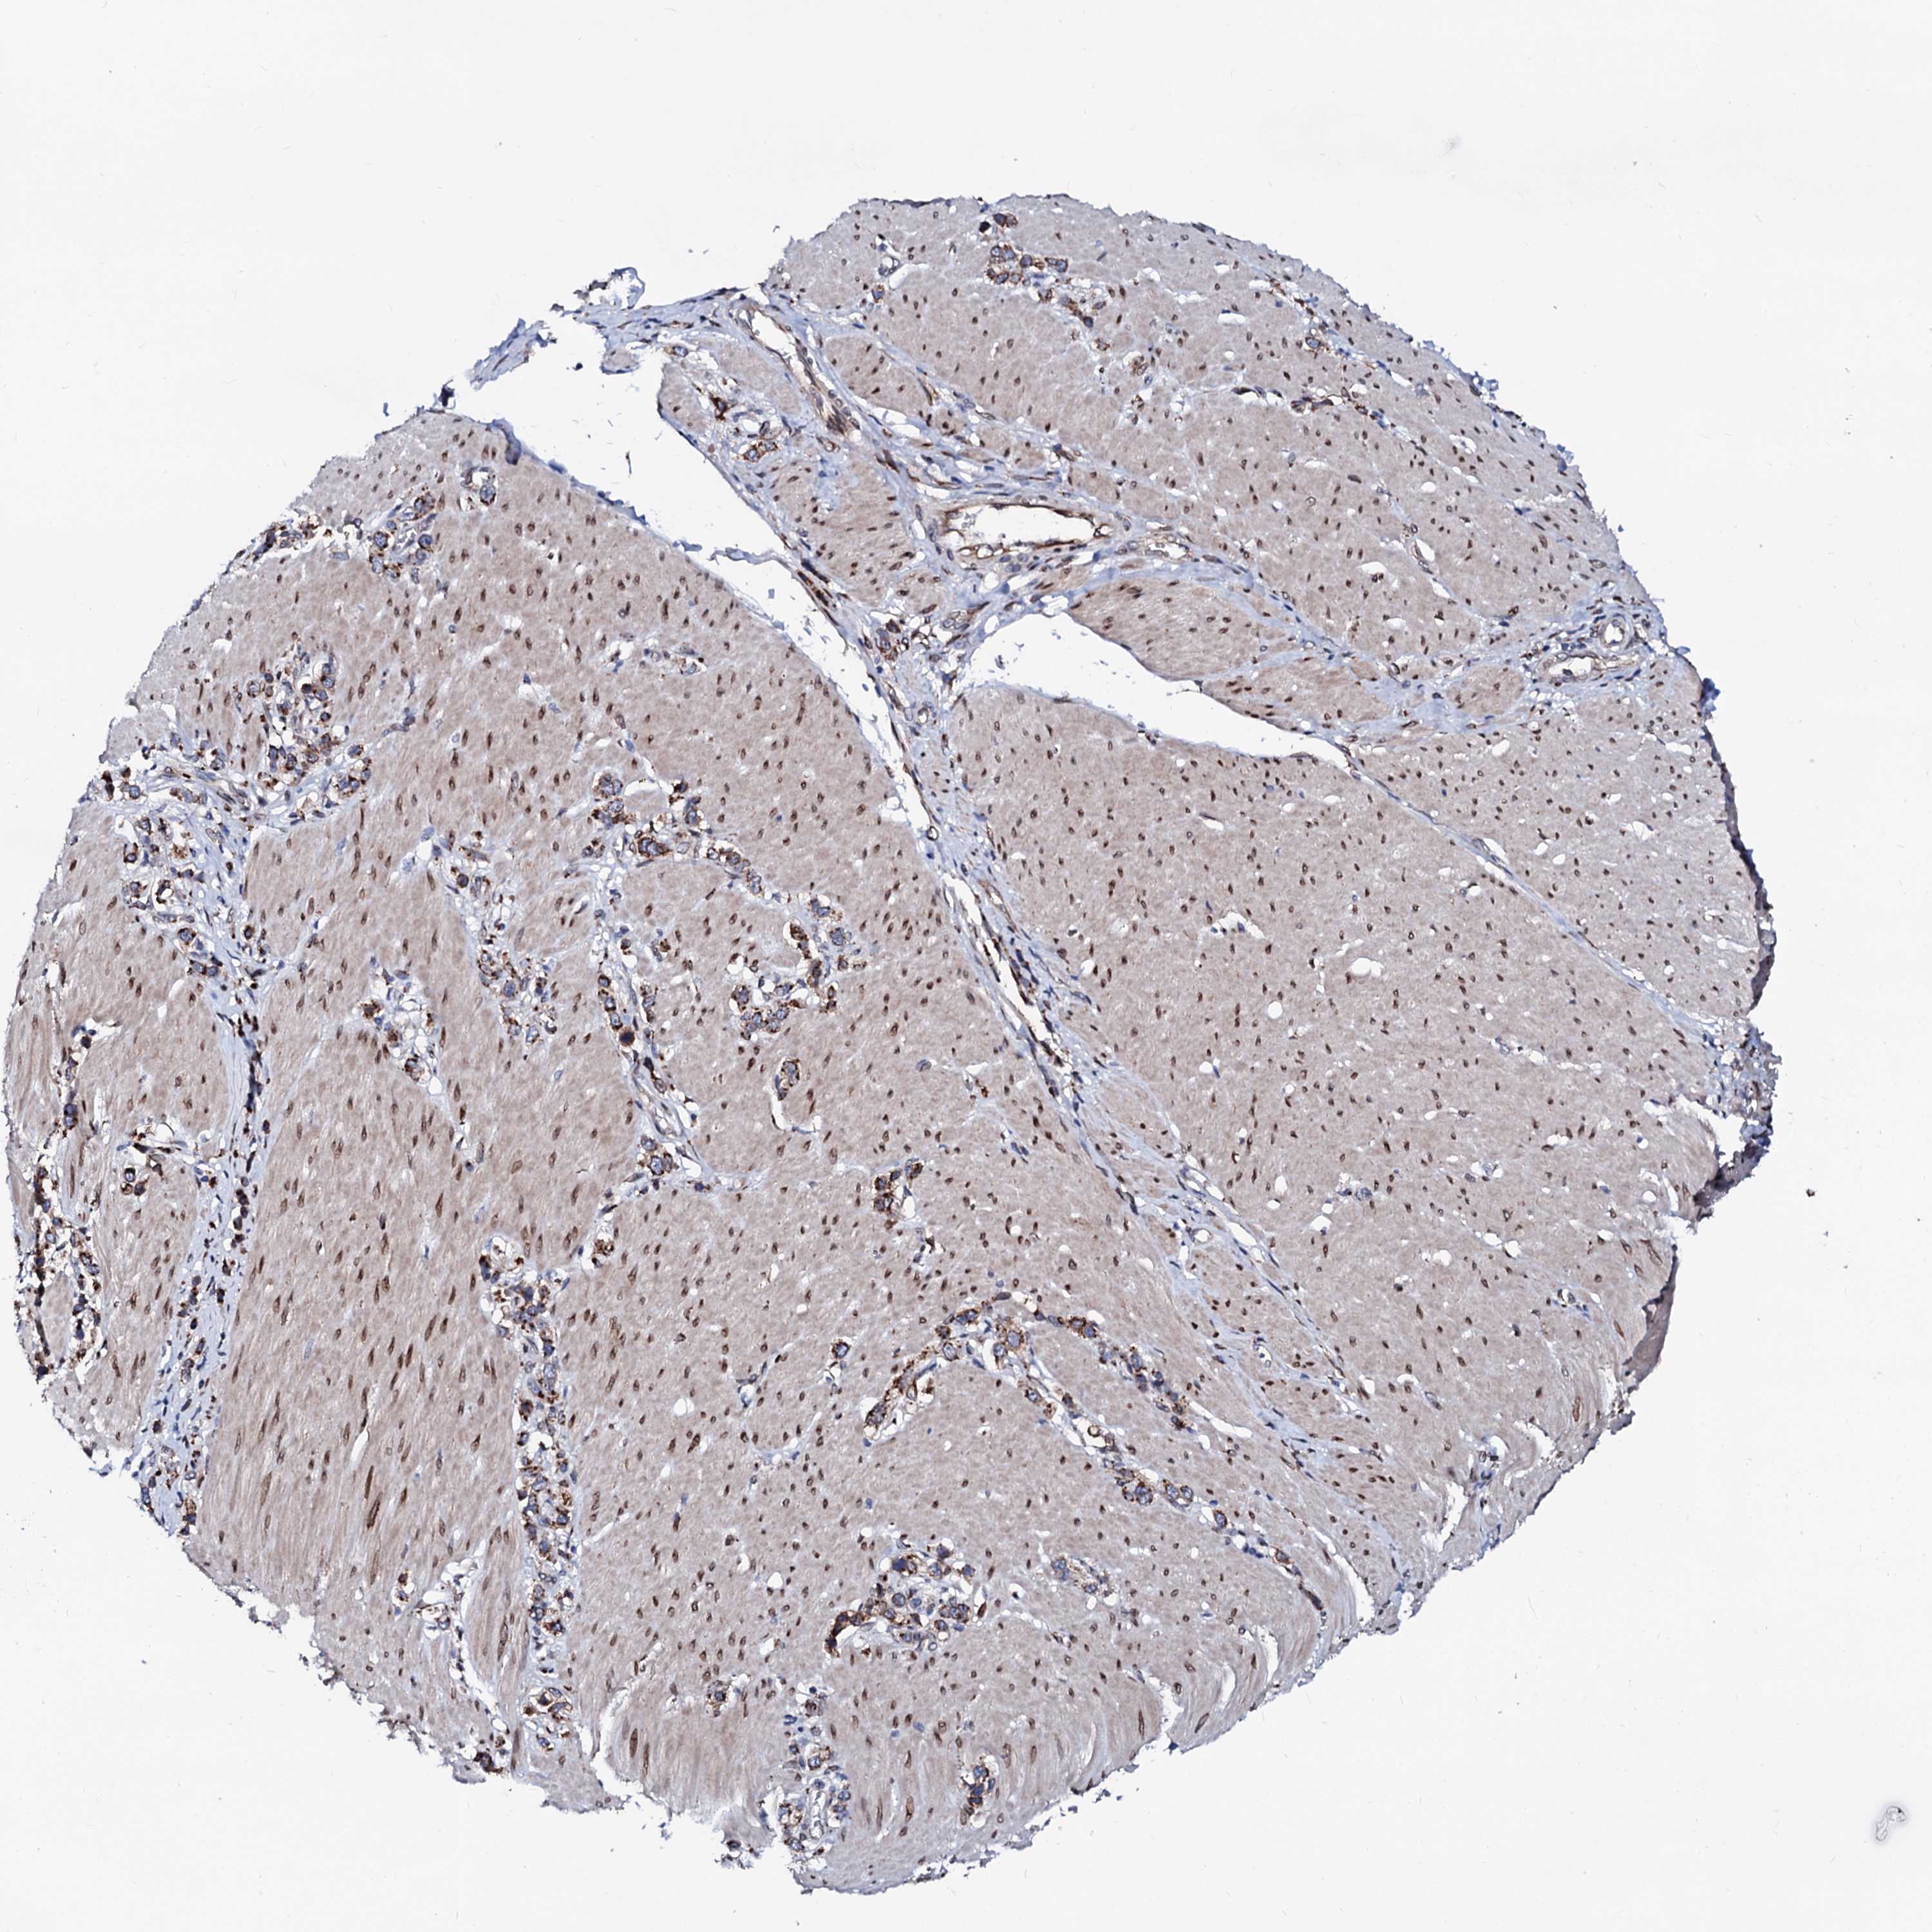

STOMACH CANCER - Protein expressioni

A mouse-over function shows sample information and annotation data. Click on an image to view it in a full screen mode. Samples can be filtered based on level of antibody staining by selecting one or several of the following categories: high, medium, low and not detected. The assay and annotation is described here.

Antibody stainingi

Antibody staining in the annotated cell types in the current human tissue is reported as not detected, low, medium, or high, based on conventional immunohistochemistry profiling in selected tissues. This score is based on the combination of the staining intensity and fraction of stained cells.

Each image is clickable and will lead to virtual microscopy that enables deeper exploration of all samples and also displays staining intensity scores, fraction scores and subcellular localization as well as patient and tissue information for each sample.

Antibody HPA039561

Antibody HPA048126

Staining

High

Medium

Low

Not detected

Intensity

Strong

Moderate

Weak

Negative

Quantity

>75%

75%-25%

<25%

None

Location

Nuclear

Cytoplasmic/membranous

Cytoplasmic/membranous,nuclear

Adenocarcinoma, NOS